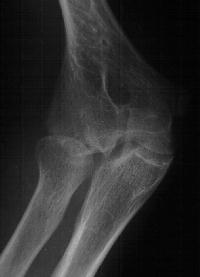

Plain films show humeral osteophytes and posttraumatic changes of the capitellum and radial head.